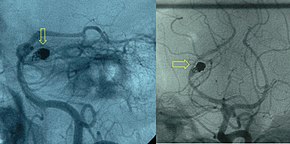

If a cerebral aneurysm is identified on angiography, two measures are available to reduce the risk of further bleeding from the same aneurysm: clipping[46] and coiling.[47] Repair should take place within 24 hours if possible.[4] Clipping requires a craniotomy (opening of the skull) to locate the aneurysm, followed by the placement of clips around the neck of the aneurysm. Coiling is performed through the large blood vessels (endovascularly): a catheter is inserted into the femoral artery in the groin and advanced through the aorta to the arteries (both carotid arteries and both vertebral arteries) that supply the brain. When the aneurysm has been located, platinum coils are deployed that cause a blood clot to form in the aneurysm, obliterating it. The decision as to which treatment is undertaken is typically made by a multidisciplinary team consisting of a neurosurgeon, neuroradiologist, and often other health professionals.[5]

In general, the decision between clipping and coiling is made on the basis of the location of the aneurysm, its size and the condition of the person. Aneurysms of the middle cerebral artery and its related vessels are hard to reach with angiography and tend to be amenable to clipping. Those of the basilar artery and posterior cerebral artery are hard to reach surgically and are more accessible for endovascular management.[48] These approaches are based on general experience, and the only randomized controlled trial directly comparing the different modalities was performed in relatively well people with small (less than 10 mm) aneurysms of the anterior cerebral artery and anterior communicating artery (together the "anterior circulation"), who constitute about 20 percent of all people with aneurysmal SAH.[48][49] This trial, the International Subarachnoid Aneurysm Trial (ISAT), showed that in this group the likelihood of death or being dependent on others for activities of daily living was reduced (7.4 percent absolute risk reduction, 23.5 percent relative risk reduction) if endovascular coiling was used as opposed to surgery.[48] The main drawback of coiling is the possibility that the aneurysm will recur; this risk is extremely small in the surgical approach. In ISAT, 8.3 percent needed further treatment in the longer term. Hence, people who have undergone coiling are typically followed up for many years afterwards with angiography or other measures to ensure recurrence of aneurysms is identified early.[50] Other trials have also found a higher rate of recurrence necessitating further treatments.[51][52]